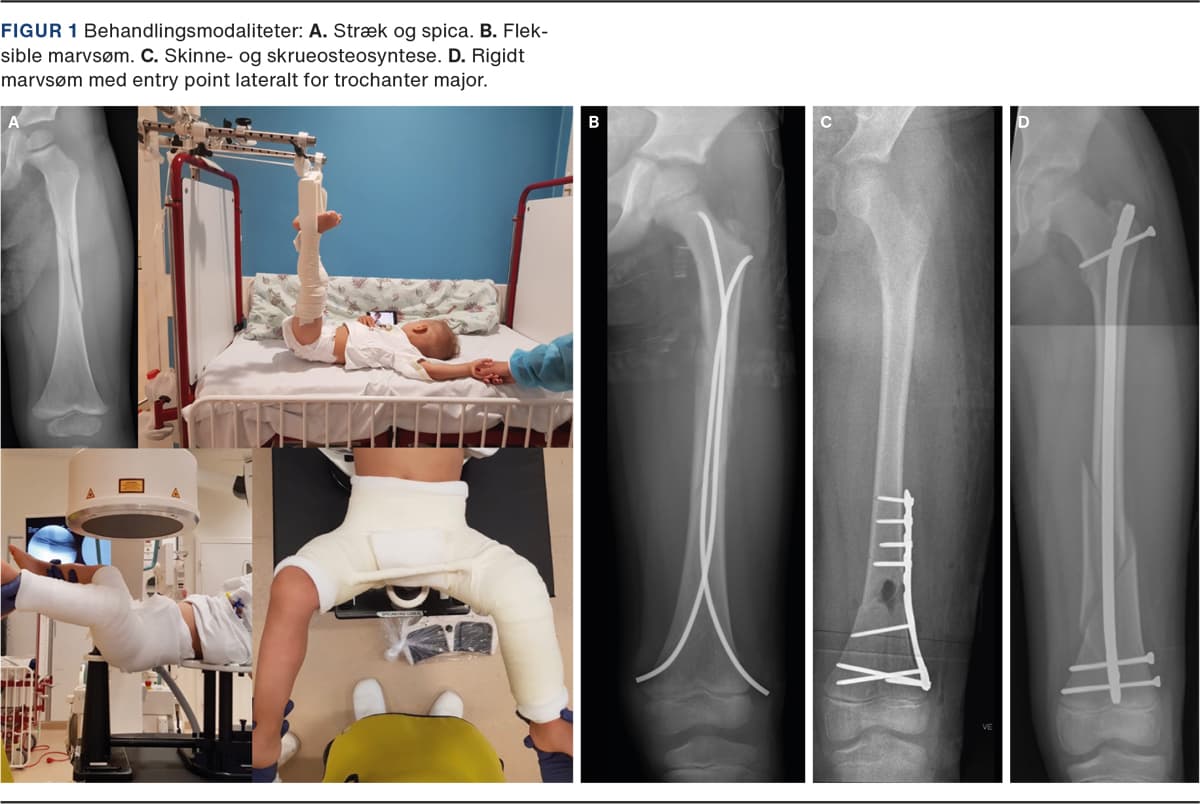

Behandlingsindikation for nonoperativ vs. operativ behandling og målsætning mhp. at genoprette benets længde, akse og rotation afhænger af barnets alder, vægt og frakturtype (Figur 1). Vejledende acceptable fejlstillinger for skaftfraktur fremgår af Tabel 1 [7].

Til de mindre børn benyttes vertikalt galgestræk (Bryants traktion), hvor begge ben ophænges med kontravægt, så barnets baller akkurat løftes fri af underlaget (Figur 1A). Når barnet hænger i strækket, kan der foretages røntgenkontrol, og forkortning samt rotationsfejlstilling kan helt eller delvist korrigeres. Longitudinelt stræk (Hamilton-Russell-traktion) giver mulighed for at færdigbehandle større børn, men dette setup forefindes kun få steder. Hudkomplikationer som sår og irritation er hyppige komplikation i forbindelse med plasterstræk (Figur 2A).

Alternativet til plasterstrækbehandling er anlæggelse af en hoftespica i generel anæstesi (Figur 1A). I Nordamerika har man i en del år med gode resultater behandlet femurfrakturer hos børn med hoftespica frem for strækbehandling [10, 11]. Anlæggelse af en hoftespica kræver specielt lejringsudstyr og kompetent personale, hvorfor behandlingen ofte kun foregår på et børneortopædisk center. Spicabehandling har traditionelt været foretaget efter få dage med strækbehandling i ønsket om at få genskabt længden på frakturen og opnå begyndende heling og stabilitet i frakturen. I nyere studier er det dokumenteret, at man i flere tilfælde kan anlægge spica tidligt (< 48 timer) og dermed reducere indlæggelsestiden [12, 13]. Det er også en praksis, som i stigende omfang benyttes i Danmark.

Ved operativ behandling af femurfrakturer hos børn med åbne vækstzoner benyttes der i dag overvejende den ovennævnte teknik med indsættelse af fleksible marvsøm (Figur 1B). Metoden er udviklet ved børnehospitalet i Nancy i Frankrig. Teknikken kræver oplæring i korrekt anvendelse. Mest almindeligt benyttes en retrograd teknik, hvor to fleksible marvsøm indsættes lateralt og medialt fra metafysen (Figur 1B). Ved at forbøje marvsømmene i c-form kan der opnås spredning af sømmene på niveau med frakturen, hvilket medfører trepunktsfiksation. På denne måde kan selv relativt ustabile frakturer stabiliseres [16, 17]. Teknikken kræver erfaring, og hvis man vælger en for lille sømdiameter, eller man ikke opnår tilstrækkelig trepunktsfiksation, er der risiko for frakturskred (Figur 2C). I en del tilfælde er det derudover nødvendigt at foretage åben reponering for at opnå korrekt længde, akse og rotation [18]. Gener i form af smerter og hudproblemer fra de isatte marvsøm forekommer jævnligt (Figur 2B) [19]. Intern fiksation af femurfrakturer hos børn giver dog samlet set et godt klinisk resultat, og børnene kan mobiliseres og hjemsendes hurtigt. Alternativet til fleksible marvsøm er en submuskulær skinne eller ekstern fiksation (Figur 1C).

BEHANDLING AF BØRN FRA 11 ÅR TIL UDVOKSET

Rigide låste marvsøm anvendes tiltagende hyppigt hos større børn og er vores foretrukne behandling, når marvkanalens diameter tillader det (Figur 1D, Figur 2C). En af årsagerne til dette er en stigende komplikationsrate ved anvendelse af fleksible marvsøm hos overvægtige mindre børn eller større børn [20]. Der er dog ingen fast grænse for, hvor store børn der kan behandles med fleksible marvsøm. Det nordamerikanske børneortopædiske selskab sætter den øvre grænse for at benytte fleksible marvsøm hos børn til 50 kg [15]. Desuden er der heller ikke konsensus om den nedre aldersgrænse for brugen af rigide låste marvsøm.

Ved behandling med låste marvsøm opnås der hurtigt smertefrihed og god rehabilitering [21]. Mange større børn har en marvkanal, der gør det muligt at benytte rigide, antegrade, låste marvsøm. Problemet har dog været at opnå sikker adgang til marvkanalen. Caput femoris har sin egen blodforsyning hos børn. Blodforsyningen udgår fra a. circumflexa femoris medialis [22]. Det er påvist, at entry point i fossa piriformis eller ved toppen af trochanter major påfører børn og unge en ikke ubetydelig risiko for avaskulær nekrose af caput femoris [23]. Der er udviklet nyere pædiatriske marvsøm til et entry point lateralt på trochanter major, hvilket er en mere sikker adgang til marvkanalen hos børn og unge [23]. Vækststandsning af trochanterapofysen er en teoretisk komplikation uden betydende effekt efter otteårsalderen [24].